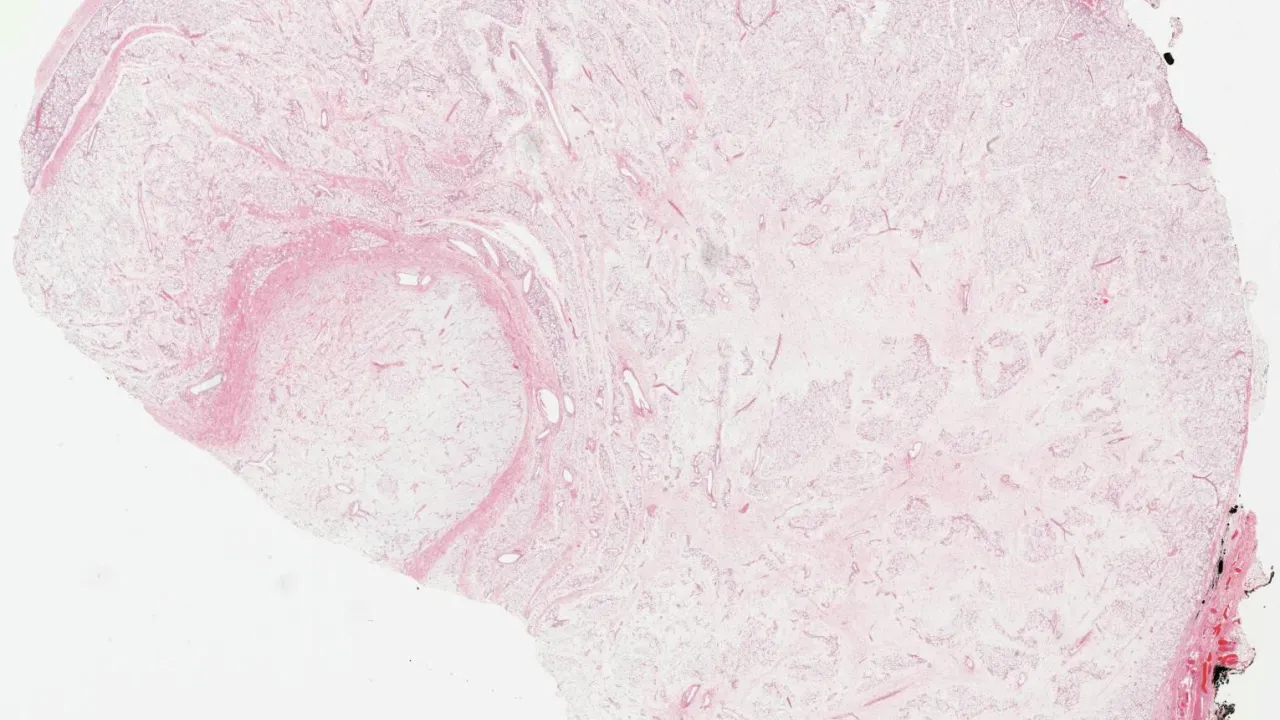

Head and Neck, Odontogenic keratocyst